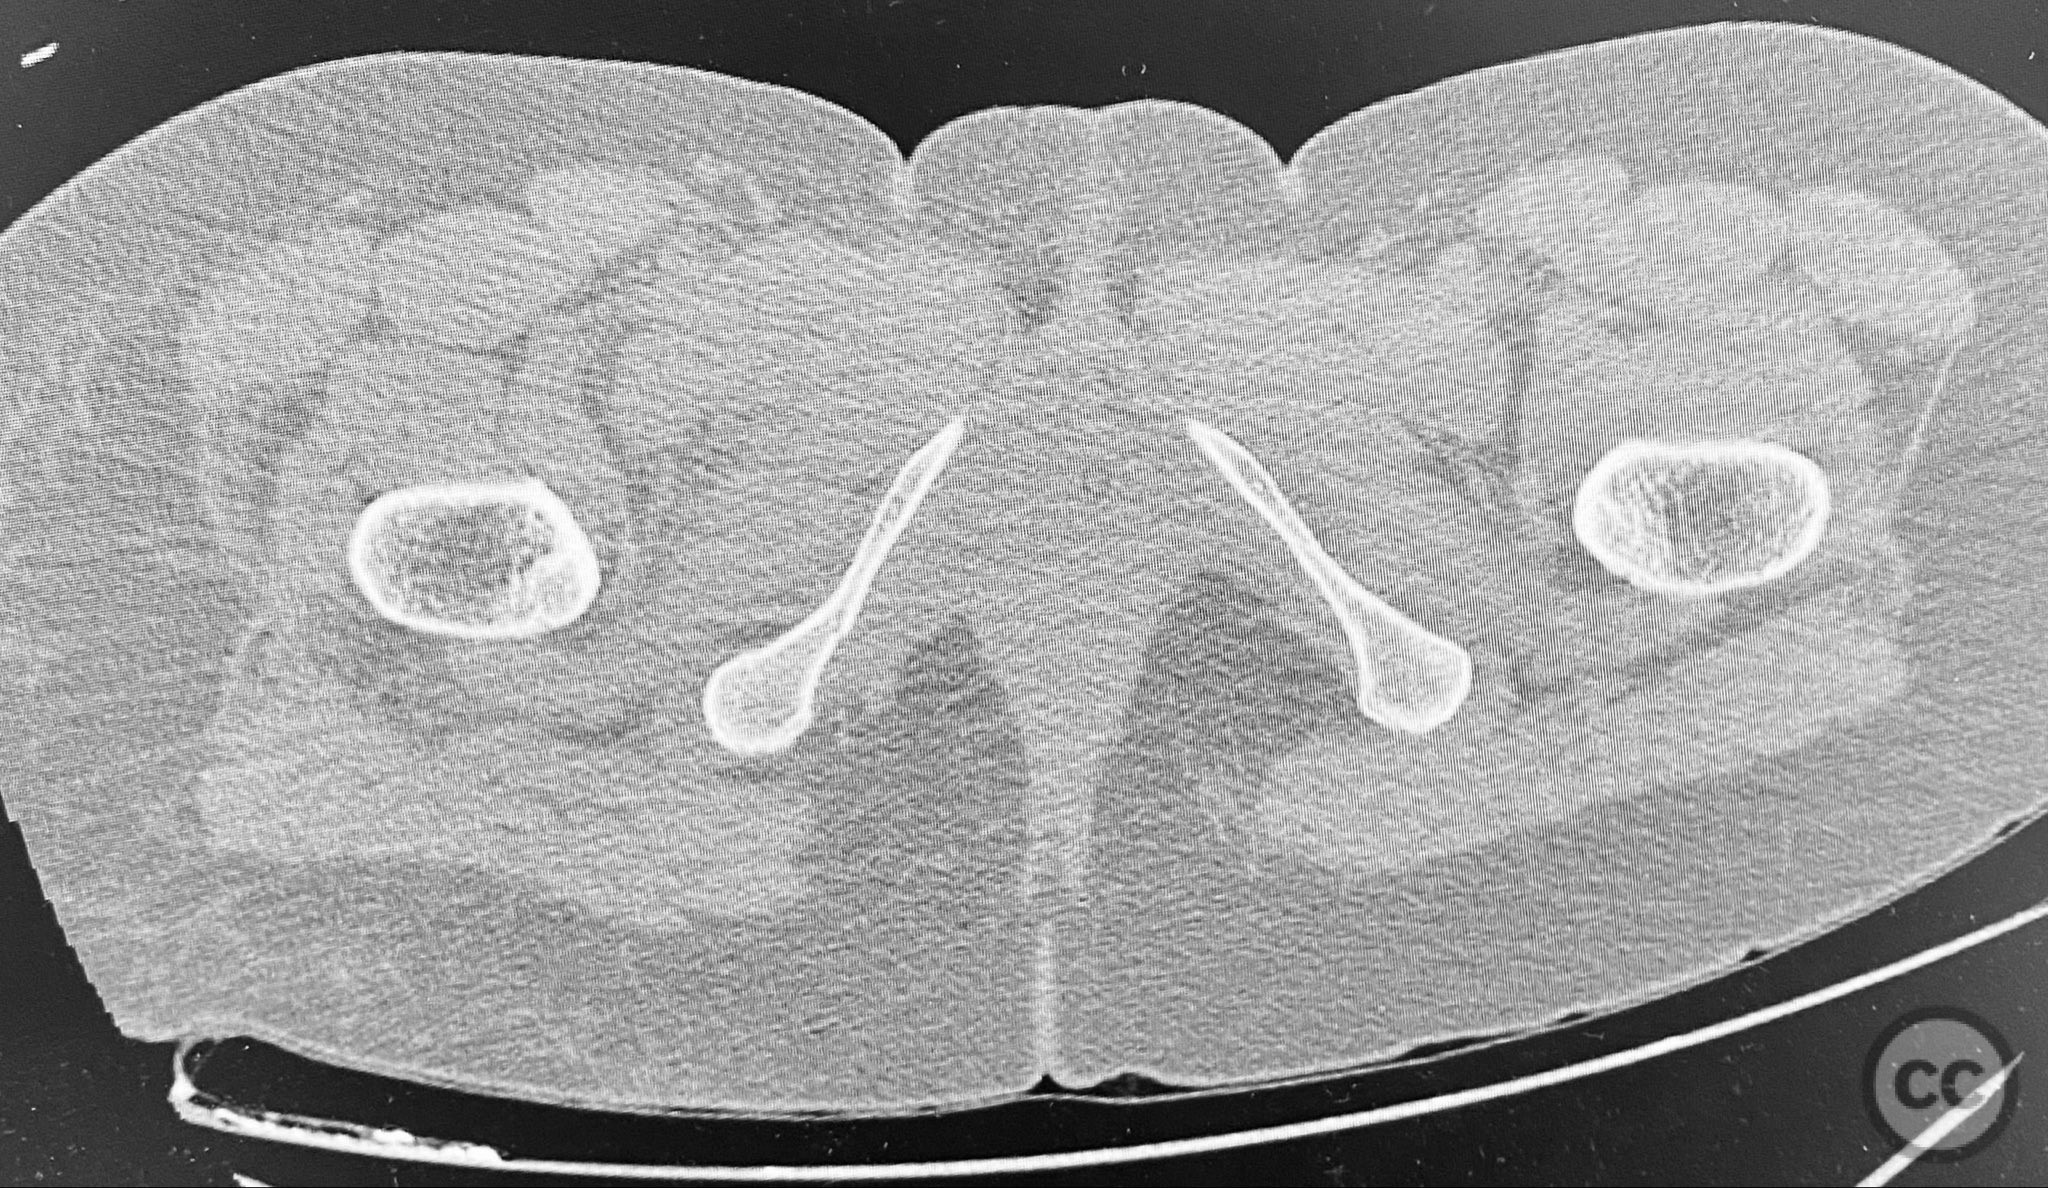

Clinical and radiological findings:  A middle-aged patient involved in a motor vehicle collision presented initially with a closed ankle fracture-dislocation and minimal pelvic complaints. Following closed reduction and splinting of the ankle, the patient developed severe pelvic pain (9/10) with any attempted movement. Neurological and vascular examination was not specified. Computed tomography demonstrated minimally displaced fractures of the posterior ilium, sacral ala, and bilateral pubic rami. AP CT surface renderings revealed subtle but clinically significant displacement and deformity of the pelvic ring, which was difficult to appreciate on standard axial images.

Anatomical surgical approach:  Percutaneous approach: Small stab incisions were made over the crista iliaca and sacral entry points as determined by preoperative imaging. Under fluoroscopic guidance, guidewires were advanced across the sacroiliac joint and sacral ala as indicated. Cannulated screws were inserted percutaneously to stabilize the unstable posterior pelvic ring and rami fractures.